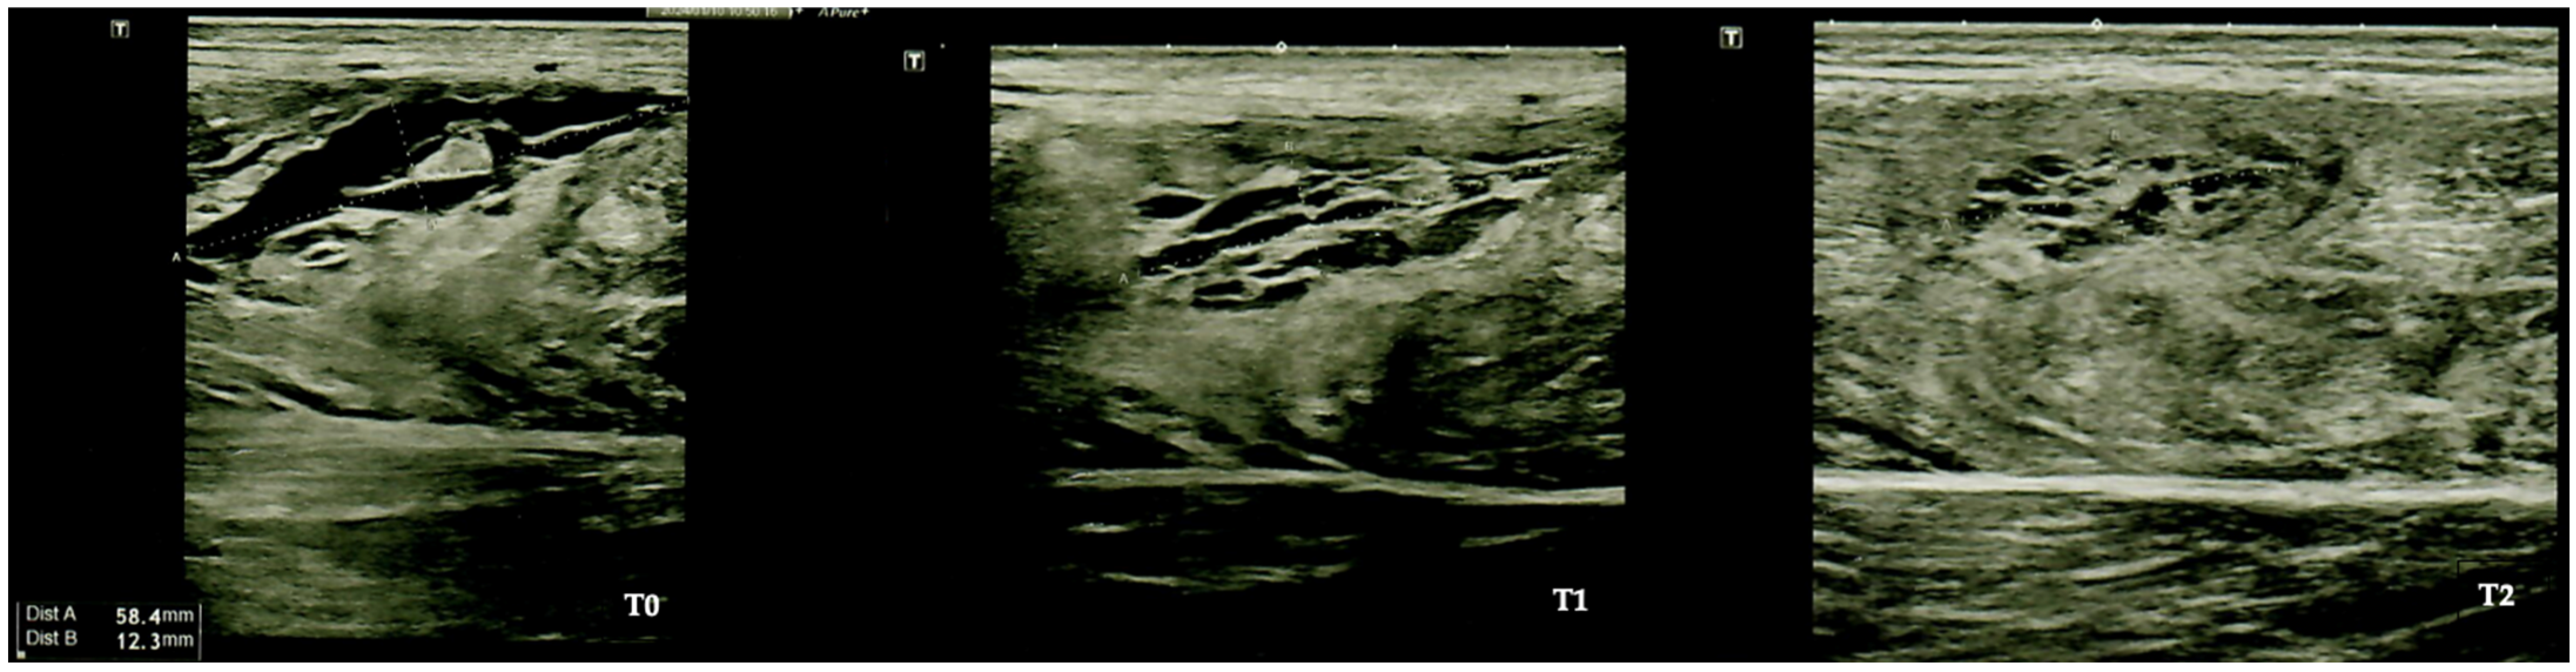

The evaluation of muscle improvements using panoramic B-mode ultrasound involves the use of a sonographic device (Toshiba Aplio 400 ultrasound system, Tokyo, Japan). This advanced diagnostic tool was equipped with a 9 MHz linear array transducer that has a width of 60 mm; the tool was employed by a qualified operator [32]. Panoramic ultrasound imaging has been repeatedly demonstrated as a valuable tool for monitoring muscle injuries.

Furthermore, through ultrasound evaluation, we observed a significant improvement in the echostructure of the recovery from muscle injury, as depicted in Figure 2.

Figure 2. Ultrasound evaluation. T0: baseline; T1: at the end of the treatment; T2: four weeks after the end of the treatment.